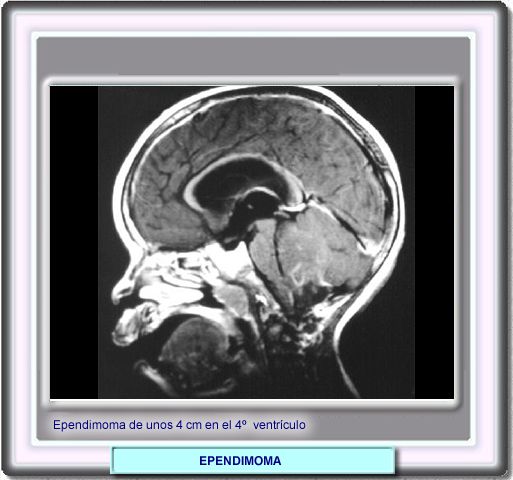

Imagen sagital después de la administración i.v. de un contraste mostrando una masa de unos 4 cm en al cuarto ventrículo. Tanto la resonancia como la TC son suficientes para el diagnóstico

Los ependimomas son el tercer tipo de tumor cerebral más común en los niños y suponen un 15% de los cánceres de la fosa posterior. Por regla general, los tumores emergen de las células del epéndimo que tapizan el cuarto ventrículo. Usualmente, el tumor se expande a través del foramen de Magendie y el agujero de Luschka. A menudo, estos tumores están calcificados y pueden presentar un amplio componente cístico.